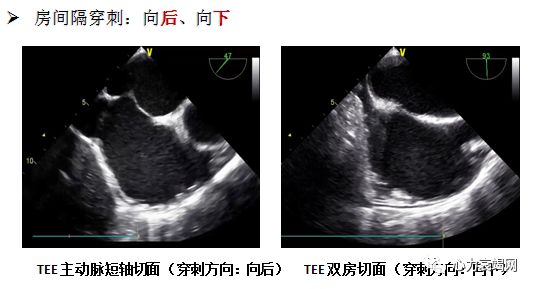

房间隔穿刺:TEE指引下, 用8 FrSL1 穿刺套件, 房间隔后下方